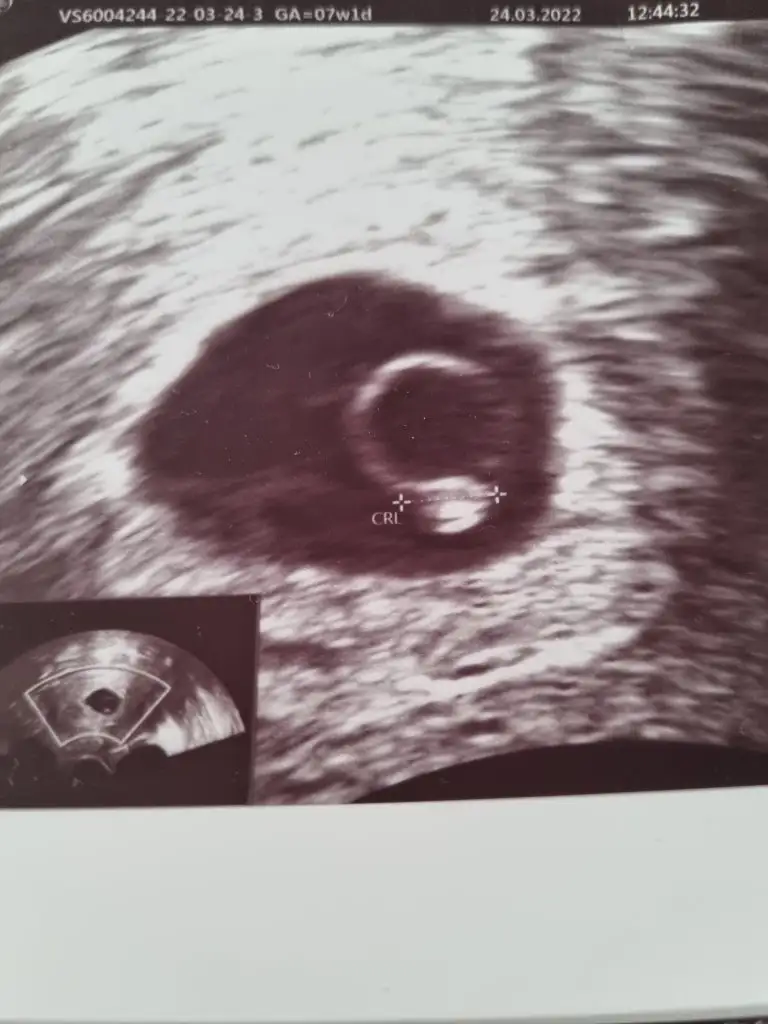

Merhaba 7+1 vajınal ultrason

5 ve 14. haftaya kadar olan ultrason fotolarınızı paylaşın. Vajinadan mı yoksa karından mı çekildiğini ve kaç haftalık olduğunu da mutlaka belirtin.